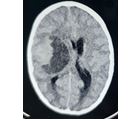

Results: During the period of this study, we made some changes in techniques and treatment strategies for treating patients with neurosurgical problems. Our data revealed, 18 patients were presented with extra-dural haemorrhage (EDH), depressed fracture was detected in 42 of the patients, and hydrocephalus 12, abscess 5, tumor were 8, and sub-dural haemorrhage (SDH) was encountered in 41 patients.

During the period of this study, we made some changes in techniques and treatment strategies for treating patients with neurosurgical problems. This study included 136 patients, male were 111 (81.6%), female were 25 (18.4%). The most frequent age group was ranging from 11 to 20 years which was detected in 18.4% of the patients (Table 1). Regarding diagnosis of the patients, sub-dural haemorrhage (SDH) was encountered in 41 patients (30.1%), the sub classes of SDH showed that, patients with acute SDH were 6 (14.6%), sub-acute were 17 (41.4%) and chronic were 19 (46.3%). Our data revealed, 18 patients were presented with extra-dural haemorrhage (EDH), depressed fracture was detected in 42 of the patients, and hydrocephalus 12, abscess 5 and tumor were 8 (Table 2). In this study 124 (91.1%) of the patients were recovered Immediately from anesthesia.